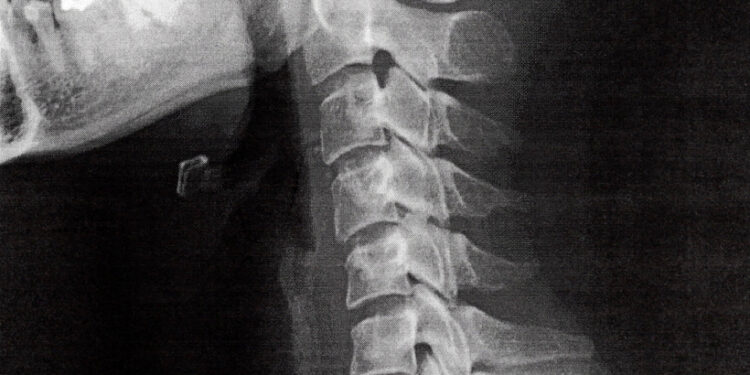

Tikslesni diagnostiniai tyrimai yra rentgeno nuotraukos, kompiuterinė tomografija (KT) arba magnetinio rezonanso tomografija (MRT), kurie padeda tiksliai nustatyti stuburo formas, pakitimus bei nervų pažeidimus.